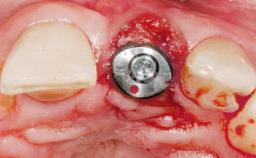

A 33-year-old female patient presented with an upper left central incisor that required extraction after a failed endodontic therapy. The tooth had been traumatized when the patient was a teenager and had undergone several endodontic treatments, including two apicectomy procedures. The patient was in good health and did not smoke. Clinical examination showed that the patient had a high lip line. In full smile, the gingival margins of the upper teeth were visible to the first molars. The gingival margins of central incisors 11 and 21 were only just showing. Examination of tooth 21 confirmed that the tooth was mobile and had hypererupted by 1 mm.

Type of Implants One-Piece

Placement Protocol Immediate implant placement

Tooth Site Maxillary incisor or canine

Socket Morphology Single-root socket

Socket Integrity Damage to one or more bone walls

Bone Volume Damage to one or more socket walls